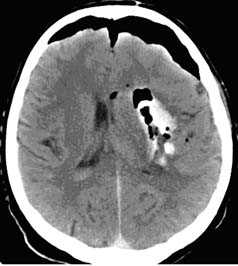

з) Паренхиматозные гематомы. Паренхиматозные гематомы вызываются разрывом небольшого паренхиматозного сосуда и не связаны с корковыми ушибами. Они могут возникать через несколько дней после травмы.

Ключевые данные визуализации:

- Гиперденсное скопление крови в белом веществе лобных и височных долей или базальных ядрах.

е) Ушибы субкортикального локализации. Ушибы субкортикальной локализации — еще один вид первичной травмы головного мозга в связи с разрывом проникающих сосудов. Встречаются только при тяжелой травме.

- Несколько точечных кровоизлияний в базальных ядрах (гиперденсные на неконтрастной КТ).

Эпидуральная гематома (слева), которая возникает в результате разрыва оболочечной артерии,

как правило, на фоне перелома кости черепа, представляет собой скопление артериальной крови

между твердой мозговой оболочкой и внутренней поверхностью черепа.

При субдуральной гематоме (справа) разрыв мостиковых вен между головным мозгом

и верхним сагиттальным синусом приводит к скоплению крови между паутинной и твердой мозговыми оболочками.